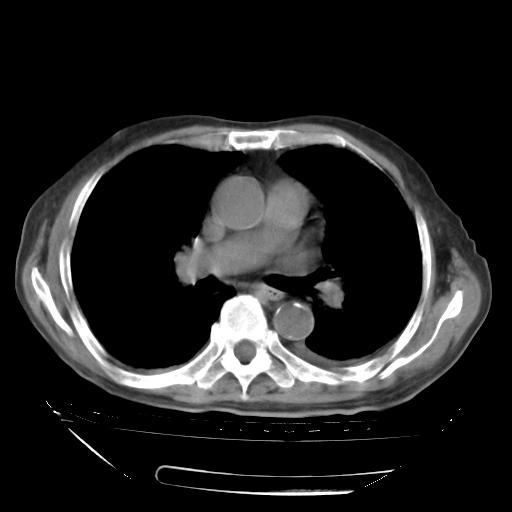

经过24天治疗,岳父的病情基本稳定。生活基本可以自理,可以下床活动。呼吸困难早已消失。体温基本正常。

只是甲强龙用80mg时血小板升到正常,改为60mg后又降到63×10*9/L。

主要治疗甲强龙80mg×14天,60mg×10天;同时抗结核(异烟肼+利福平+乙胺丁醇)。环磷酰胺0.1 tid 10天。

特别感谢胡教授、高管、桃子版主给出关键的治疗建议。桃版把所有肺部影像和全部临床资料请所在医院呼吸科、感染病科、结核科、临床免疫科专家会诊。临床免疫科专家制定了完整的治疗方案。